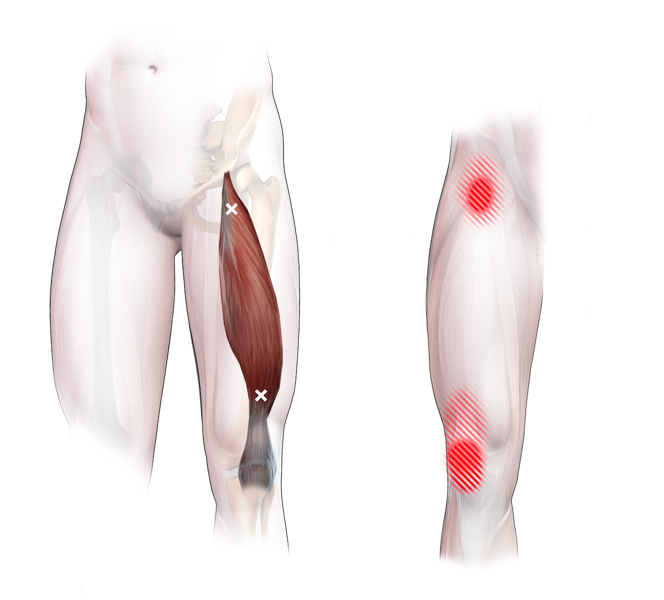

Spieren (Nederlands)

Spieren (nederlands)

Spieren (Latijn)

Spieren (latijn)